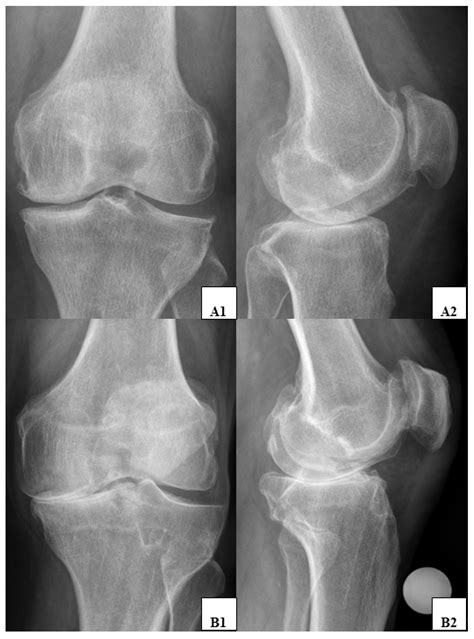

A Lateral Knee Xray is a type of radiographic imaging that captures a side view of the knee joint. This view is essential for evaluating the alignment of the bones, the condition of the joint spaces, and the presence of any abnormalities such as fractures, dislocations, or arthritis. The lateral view complements other views, such as the anteroposterior (AP) and oblique views, to provide a comprehensive assessment of the knee.

Interpreting a Lateral Knee Xray

Interpreting a Lateral Knee Xray requires a trained eye and knowledge of knee anatomy. Here are some key points to look for:

• Bone Alignment: Ensure that the bones are properly aligned. Any deviation can indicate a fracture or dislocation.

• Joint Spaces: Check the joint spaces for any narrowing, which can suggest arthritis or other degenerative conditions.

• Fractures: Look for any breaks or cracks in the bones, which can indicate a fracture.

• Soft Tissue Signs: While not always visible, soft tissue injuries can sometimes be inferred from the presence of joint effusion or other indirect signs.